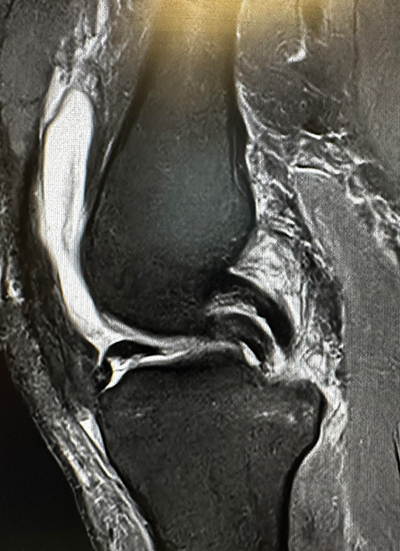

Figure 1

Bucket handle meniscal tears are longitudinal/vertical, full thickness tears in which the attachment of the anterior and posterior roots are still intact, but often involve a large portion of the posterior horn and mid body. Bucket handle meniscal tears can be considered one of the more serious types of meniscal tears. They usually represent 10-15% of all symptomatic meniscal tears. They typically occur in younger adults after the sudden twist or pivot of the knee. However, bucket handle type tears can also occur in an older population. They characteristically have not only pain, but also locking of the knee. They can cause mechanical blocks when the torn fragment displaces in the notch of the knee. This can often be seen on an MRI, which is called a “double PCL sign.” (Figure 1) A sagittal midline cut of the knee shows two objects, which both look like the PCL.